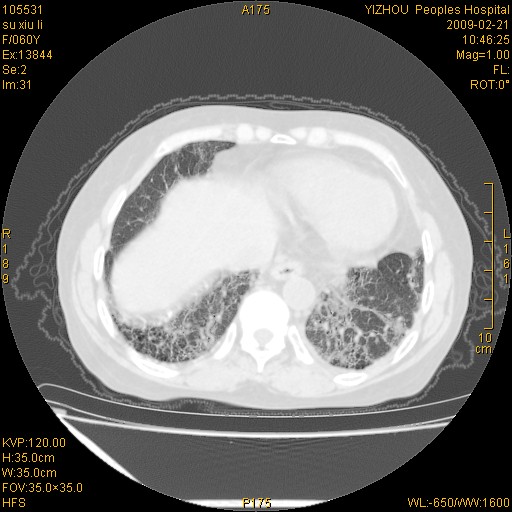

标题: CT18259:两肺间质纤维化? [打印本页]

标题: CT18259:两肺间质纤维化?

女,60岁,反复咳嗽1月。

两肺支扩,以肺为著合并双肺较广范纤维化病变。建议除外结核等病变。

两下肺支扩

符合间质感染,部分纤维化表现

特发性间质纤维化

特发性间质纤维化伴支扩!